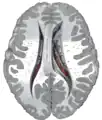

Transverse Cut of Brain (Horizontal Section), basal ganglia is blue | |

Together with the putamen, the caudate forms the dorsal striatum, which is considered a single functional structure; anatomically, it is separated by a large white matter tract, the internal capsule, so it is sometimes also referred to as two structures: the medial dorsal striatum (the caudate) and the lateral dorsal striatum (the putamen). In this vein, the two are functionally distinct not as a result of structural differences, but merely due to the topographical distribution of function.